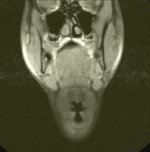

Schädel

seitlich

T2-gewichtetes

MRT |